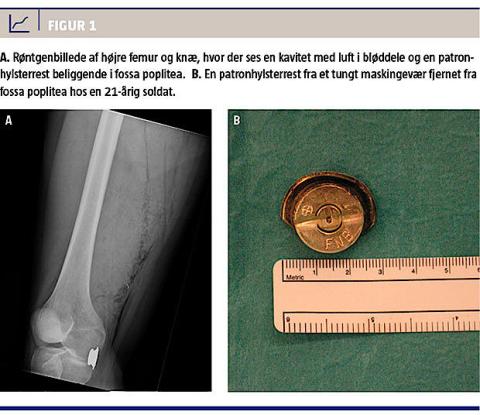

Objektivt var der et savtakket sår på 1,5 × 1 cm proksimalt og anteriort på femur. Der var ingen igangværende blødning og ingen synlige krudtpartikler, sod eller kontusionsring om såret. Quadricepsmuskulaturen var palpationsøm, men muskulaturen var ikke spændt, og femur var ikke omfangsforøget. Der var derimod udtalt ømhed ved palpation i fossa poplitea. Der kunne ikke lokaliseres et udskudshul. Benet var velvaskulariseret, og der var ingen neurologiske udfald. Paraklinisk var der et hæmoglobinniveau på 8,6 mmol/l (referenceværdi: 8,3-10,5 mmol/l). Røntgen af højre femur viste en kavitet med luft i bløddelene og en ca. 3 cm lang patronhylsterrest beliggende i fossa poplitea (Figur 1A). Supplerende computertomografiangiografi viste luft både subkutant og muskulært fra et indskudshul til en patronhylsterrest beliggende i caput mediale af gastrocnemiusmuskulaturen. Der blev ikke påvist fraktur eller tegn på ekstravasation.

I generel anæstesi blev der foretaget eksploration og revision af sårkaviteten ved indskudshullet og åben fjernelse af patronhylsterresten i fossa poplitea (Figur 1B). Der var ingen kar- eller nervelæsioner. Såret ved indskudshullet blev behandlet åbent, og operationssåret i fossa poplitea blev lukket primært. Der blev indledt antibiotisk behandling med intravenøst givet cefuroxim og metronidazol. Tre dage efter indlæggelsen blev patienten udskrevet. Da var han afebril, sårene var uden infektionstegn, og paraklinisk var C-reaktivt protein-niveauet og leukocytniveauet inden for normalområdet. Der blev behandlet med amoxicillin/clavulansyre og metronidazol givet peroralt i yderligere en uge, og behandlingen blev afsluttet via patientens egen læge. Der var ingen sequelae.